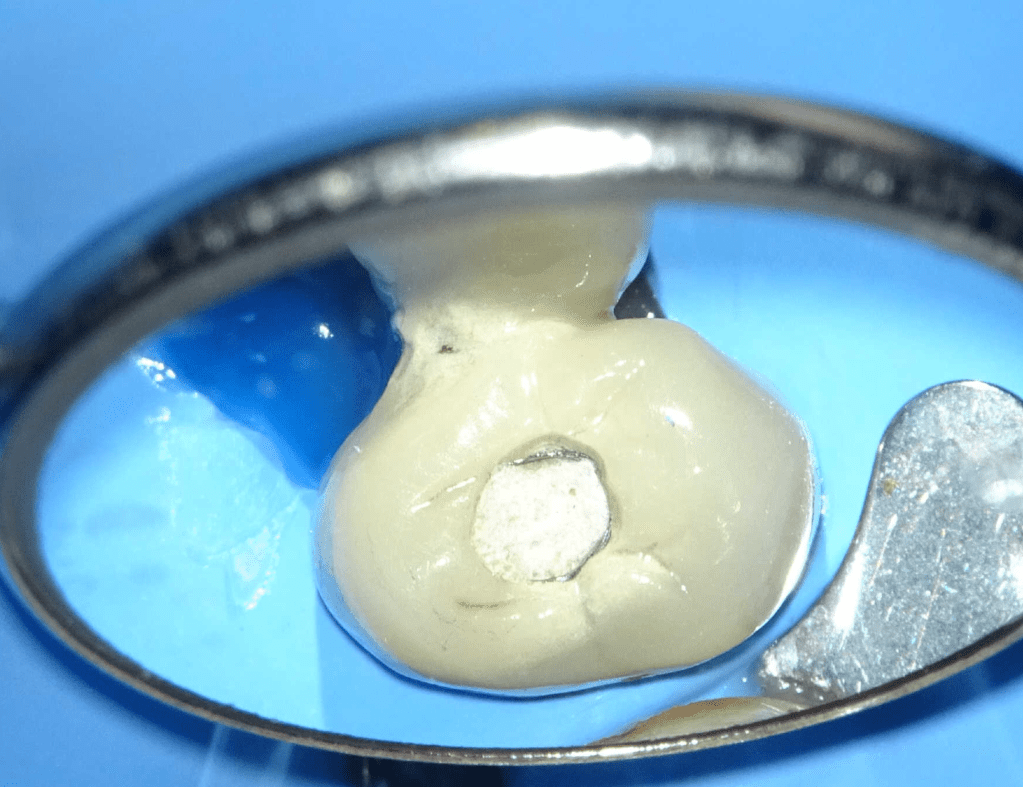

Endodoncias a traves de coronas

20 molar superior a traves de corona

Acceso ultraconservador a través de incrustación reciente